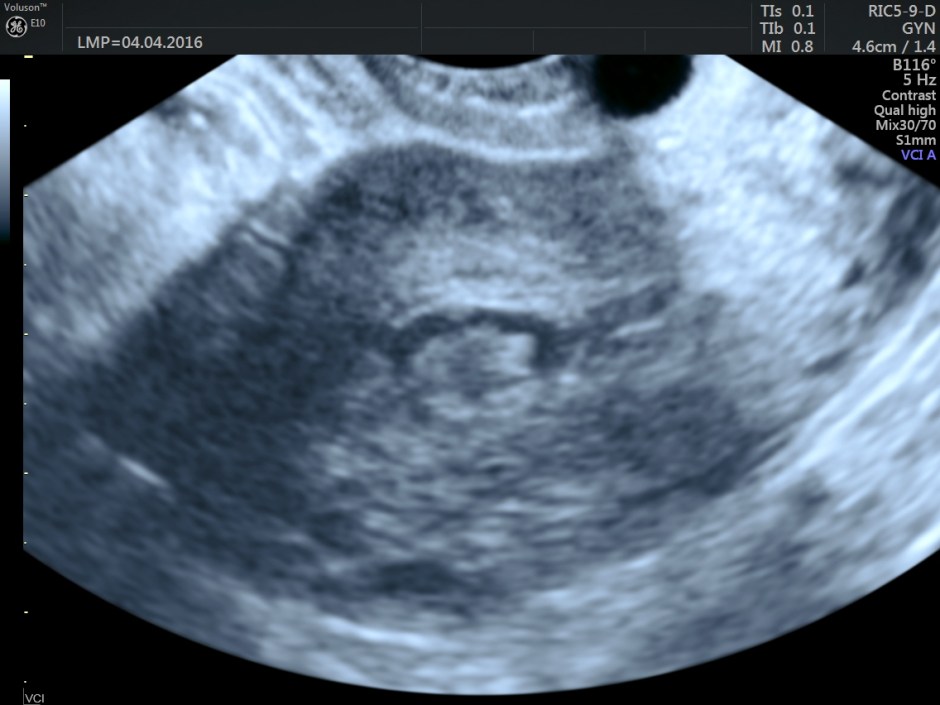

Volume contrast imaging pictures are given below:

Endometrium shows ? polypoid appearance; Irregular hypoechoic myometrial texture with some serpiginous appearance is seen.